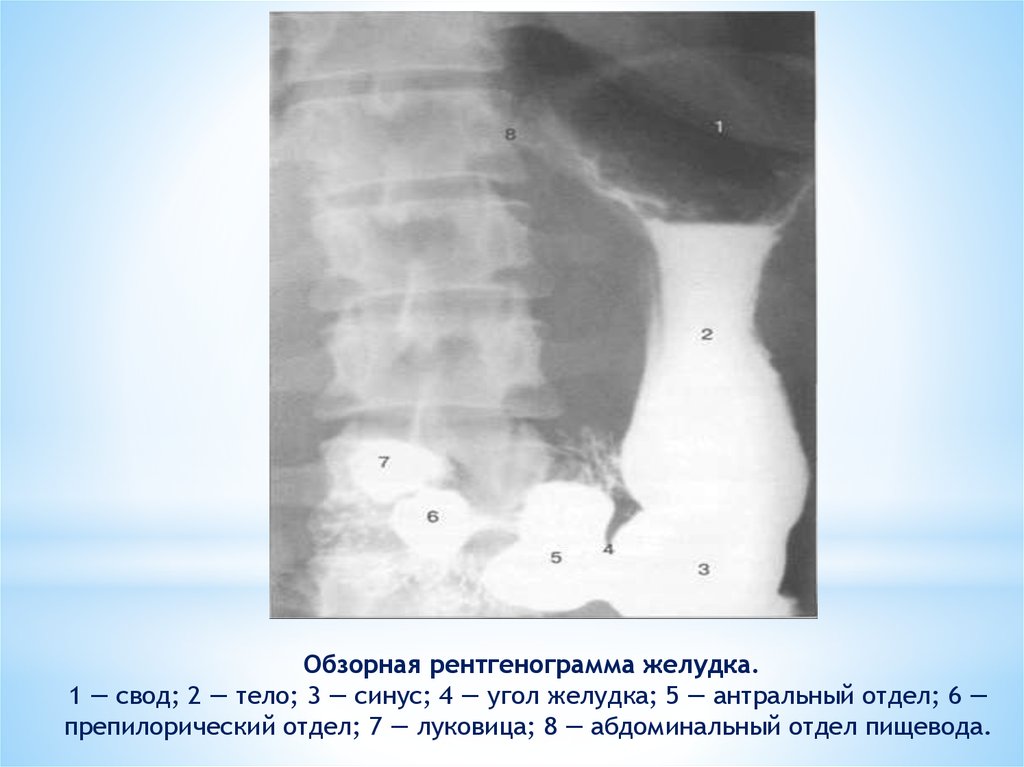

Нормы обзорной рентгенографии брюшной полости